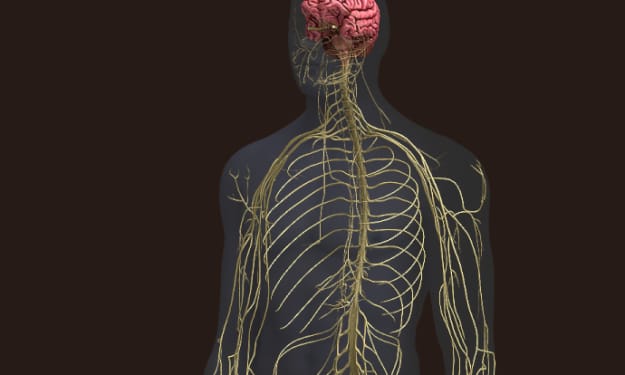

Is our nervous system this complex ???

Title: Unveiling the Power of Synapses: The Incredible Communicators of the Nervous System Introduction: What if I told you that something 1000 times thinner than a piece of paper, more numerous in you than grains of sand on a beach, holds the key to understanding the immense power of the smallest elements in your body? Welcome to the world of synapses, the meeting points between neurons that transform the structure of your nervous system into an extraordinary network of communication and intelligence.

By RAMYA VENUGOPAL3 years ago in Humans

Is our nervous system this complex ???

Title: Unveiling the Intricacies of Neuronal Communication: The Power of Action Potentials Introduction: Imagine a world where every thought, feeling, and action can be communicated by simply pressing a button. It would be like using a simplistic app that emits a constant and uniform ping, conveying everything from "I'm cold" to "I love churros" to "I need to breathe." Interestingly, this concept mirrors how neurons send electrical impulses responsible for all our actions, thoughts, and emotions. Neurons transmit signals through a remarkable phenomenon called action potentials. In this article, we will delve into the fascinating world of neuronal communication, exploring the mechanisms behind action potentials and their significance in our daily lives.

By RAMYA VENUGOPAL3 years ago in Humans

Is our nervous system this complex ???

Title: The Intricacies of the Nervous System: Understanding Its Functions and Organization Introduction Every morning, we go through various routine actions that seem mundane, such as waking up from a dream, getting dressed, having breakfast, and attending to our pets. However, these actions are not merely part of our morning rituals; they are all manifestations of the incredible capabilities of our nervous system. From processing dreams to sensing temperature changes and making decisions, our nervous system controls every aspect of our being. In this article, we delve into the fascinating world of the nervous system, exploring its anatomy, organization, communication, and the consequences of damage.

By RAMYA VENUGOPAL3 years ago in Humans